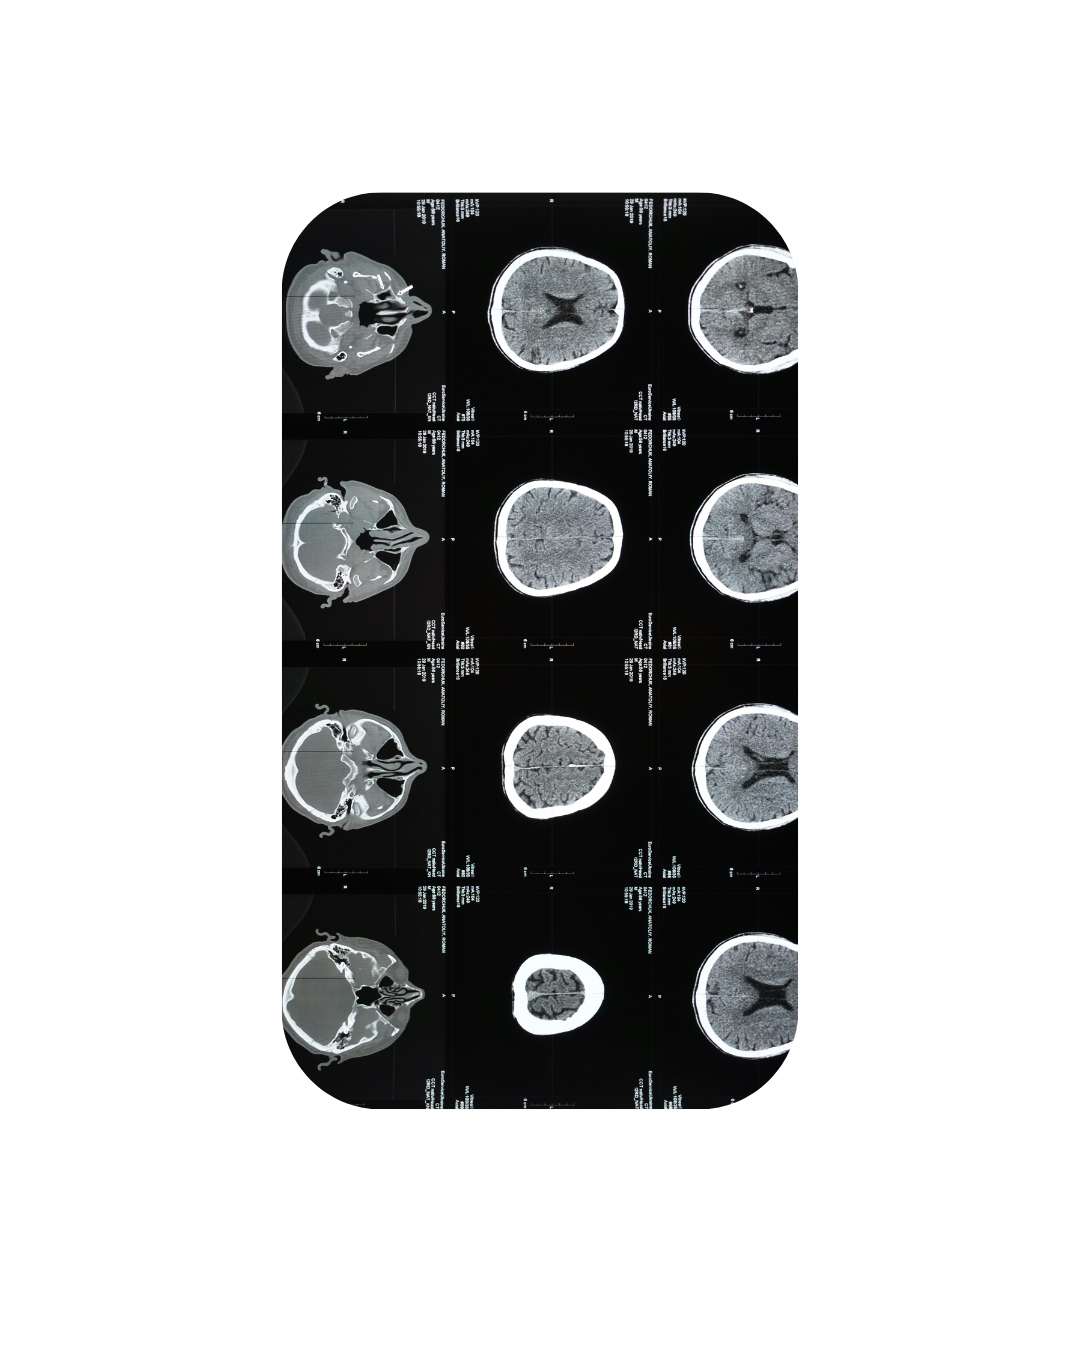

Dr. Mustafa completed a B.Sc. in Behaviour, Cognition, and Neuroscience, followed by an M.A.–Ph.D. program in Clinical Psychology with a specialization in Neuropsychology at the University of Windsor, Canada. She went on to complete her predoctoral residency in Clinical Psychology at Vancouver Coastal Health, where she trained within the Neuropsychology Track.

She has worked in hospital, rehabilitation, and outpatient settings with individuals facing a wide range of psychiatric, medical, and neurological conditions. Her training includes conducting comprehensive neuropsychological and psychodiagnostic assessments, providing individual and group psychotherapy, supporting cognitive rehabilitation, and delivering psychoeducation to patients and families. She is formally trained in Cognitive Behavioral Therapy (CBT) and Brief Psychodynamic Therapy.

Her clinical interests include brain health, emotion regulation, cognitive restructuring, and strategies that support daily productivity and overall wellbeing. She values an integrative approach guided by the biopsychosocial model, ensuring that care addresses not only symptoms but also the broader context of each client’s life.